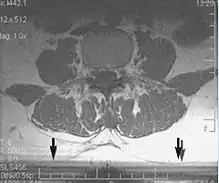

Metal artifacts occur at interfaces of tissues with different magnetic susceptibilities, which cause local magnetic fields to distort the external magnetic field. This distortion changes the precession frequency in the tissue leading to spatial mismapping of information. The degree of distortion depends on the type of metal (stainless steel having a greater distorting effect than titanium alloy), the type of interface (most striking effect at soft tissue-metal interfaces), pulse sequence and imaging parameters. Metal artifacts are caused by external ferromagnetics such as cobalt containing make-up, internal ferromagnetics such as surgical clips, spinal hardware and other orthopaedic devices, and in some cases, metallic objects swallowed by people with pica.[3] Manifestation of these artifacts is variable, including total signal loss, peripheral high signal and image distortion (Figs 3 and 4).[1] Reduction of these artifacts can be attempted by orientating the long axis of an implant or device parallel to the long axis of the external magnetic field, possible with mobile extremity imaging and an open magnet. Further methods used are choosing the appropriate frequency encoding direction, since metal artifacts are most pronounced in this direction, using smaller voxel sizes, fast imaging sequences, increased readout bandwidth and avoiding gradient-echo imaging when metal is present. A technique called MARS (metal artifact reduction sequence) applies an additional gradient, along the slice select gradient at the time the frequency encoding gradient is applied.